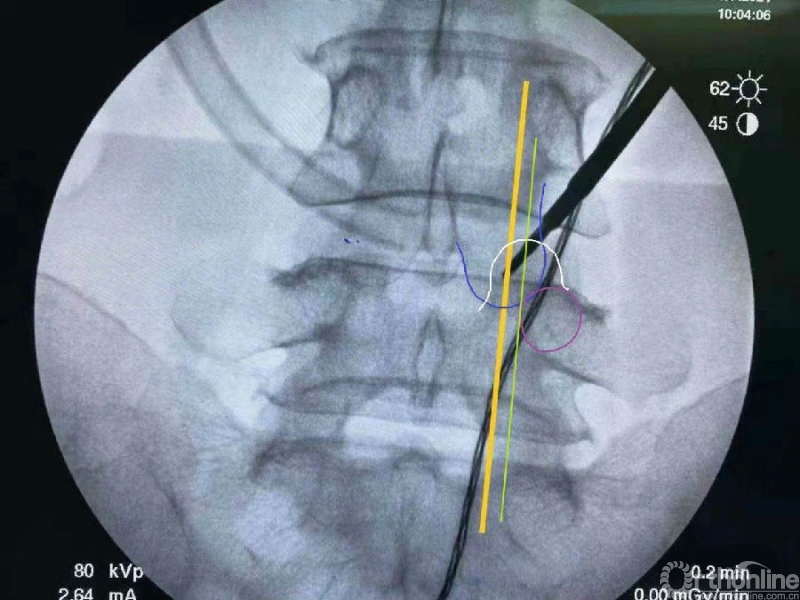

使用磨钻按照范围将下关节突内缘磨薄,然后用骨凿切除下关节突内缘显露出上关节突内缘及关节面。

术中切除下关节突内缘的范围